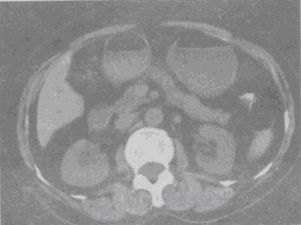

[单选题]

根据所提供的图像,最可能的诊断是

A.胰腺癌

B.胰岛细胞瘤

C.胰腺炎

D.胰腺囊腺癌

E.血管瘤

参考答案与解析: